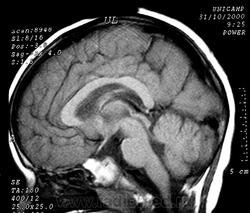

Пахигирия— уменьшение числа вторичных извилин. В пораженном полушарии нервные клетки образуют толстый недифференцированный слой с неправильно расположенными нервными волокнами и группами гетеротопных клеток. Нервные клетки незрелые. Белое вещество истончено. При этом нередко аномально развит корково-спинномозговой путь. Пахигирия может быть односторонней или двусторонней. Генерализованная пахигирия часто наблюдается при микроцефалии.